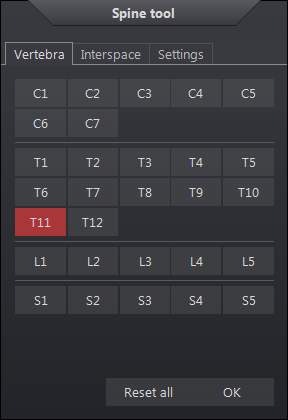

A csigolyaszámoló kurzorral címkézheti a csigolyákat és a csigolyaközöket. Ezek az előre meghatározott címkék saját megfelelő helyükön jelennek meg a képeken minden ortogonális síkban.

Csigolyaszámolás beillesztéséhez:

A jobb egérgombbal a képernyőre kattintva megjelenik a csigolyaszámolás vezérlőpanelje. Ez a mező lehetővé teszi a felhasználó számára a csigolyák és csigolyaközök címkézésének visszaállítását, és új szintek kiválasztását.

A beállítások fül a következő opciókat tartalmazza, amelyek a kezelőpanel újraindításakor visszaállnak:

| A csigolyaszámolás beállításai | Leírás |

L6-tal együtt |

L6-tal együtt L5 után |

Ellenkező irány |

Ha engedélyezve van, a címkék ellenkező irányba haladnak |

Vonalak mutatása |

Megjeleníti a tartóvonalakat a címkétől a fókuszpontig |

Panel automatikus elrejtése |

Az első csigolyaszámolás megrajzolása után automatikusan elrejti a csigolyaszámolás vezérlőpaneljét. |

Axiális, coronális, szagittális |

A csigolyaszámolások minden képen megjelennek a relatív síkban. A kép annotálásának időpontjában érvényes. |

Alkalmazott sík |

A címkéket ugyanabban a síkban jeleníti meg a képeken, mint a gerinc annotálásához használt sík. |

A megadott címkék ortogonális képeken való elhelyezéséhez az ábrának a fókuszponttól meghatározott távolságban kell metszenie a képet, amely ezután megjelenik a metszési síkban. A csigolyaszámolások automatikusan megjelennek az összes ortogonális képen. Ha a referenciakocka nincs előre meghatározva, a képeket egyenként kell címkézni. Ha a fókuszpont a megadott távolságon kívül esik, nem jelenik meg címke.